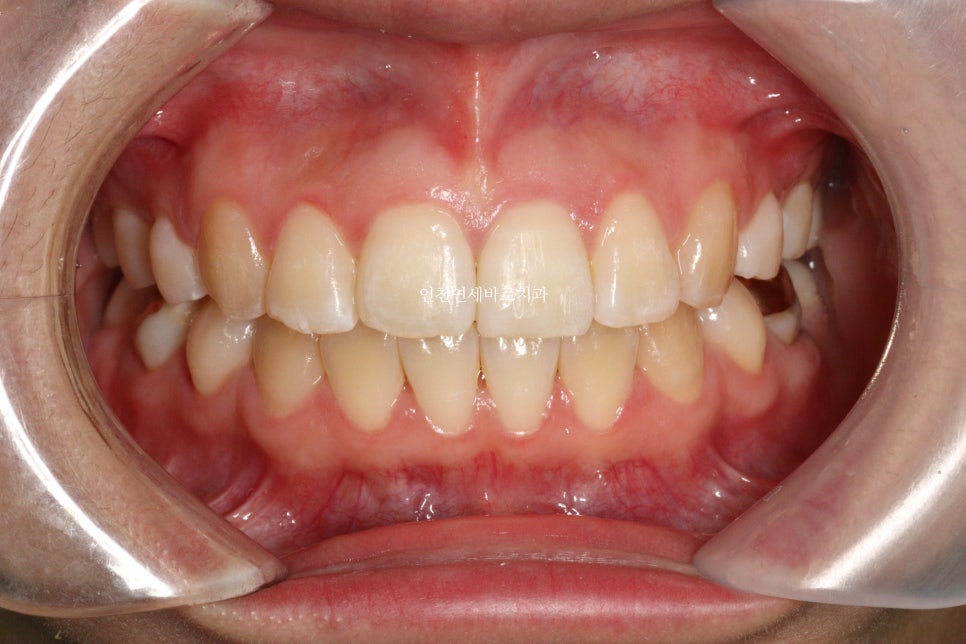

변화모습입니다.

약 3개월의 변화모습입니다.

그리고 치료가 마무리 된 후의 모습입니다.